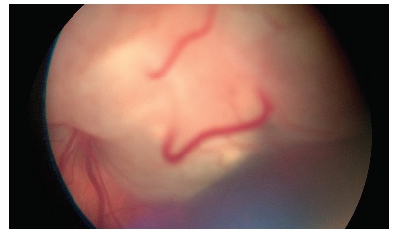

În unele cazuri, retinoblastomul este cauzat de o mutație genetică moștenită sau nou apărută, în această situație tumora apare la ambii ochi (bilateral). În alte cazuri nu există o genă defectă și doar un ochi este afectat (unilateral). Semnele clinice ale acestui cancer ocular sunt nespecifice și de cele mai multe ori sunt consecința scăderii vederii, astfel că adesea se manifestă prin apariția unui strabism (ochiul fuge), sau printr-un reflex alb al pupilei-leucorie. În cazuri avansate, ochiul poate fi roșu, mai mare, copilul poate avea stări de vomă, dureri de cap, afectare neurologică asociată.

Retinoblastom

Leucorie (reflex al alpupilei, la un pacient cu retinoblastom) https://eyewiki.aao.org/w/images/1/f/f1/Retinoblastoma_White_Reflex.jpeg